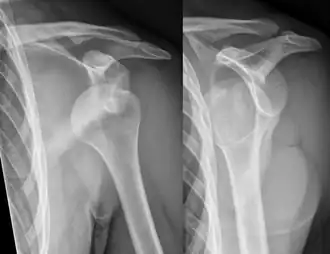

![]() Luxación anterior de hombro. | ||

En medicina, una luxación o dislocación es aquella lesión de una articulación en la que se produce pérdida del contacto entre las superficies articulares. Generalmente se debe a un traumatismo grave y no existe fractura ósea, aunque en ocasiones se asocia la luxación a una fractura.[1] La luxación escápulo-humeral o luxación de hombro tiene lugar cuando por un movimiento brusco o un trauma se produce la pérdida de contacto entre la cabeza del húmero y la cavidad glenoidea situada en la escápula. Los dos extremos óseos se desplazan de su posición normal en continuidad y la articulación pierde su función. Representa el 50% del total de las luxaciones y se manifiesta por dolor muy intenso de inicio brusco que se acompaña de imposibilidad casi total para realizar los movimientos normales del hombro.[2]

Dependiendo de la dirección en que se desplaza la cabeza del humero, puede existir una luxación anterior que representa más del 80% de los casos, una luxación posterior que no es habitual y puede pasar inadvertida durante un tiempo al provocar síntomas menos llamativos y una luxación inferior que es muy rara.[2]